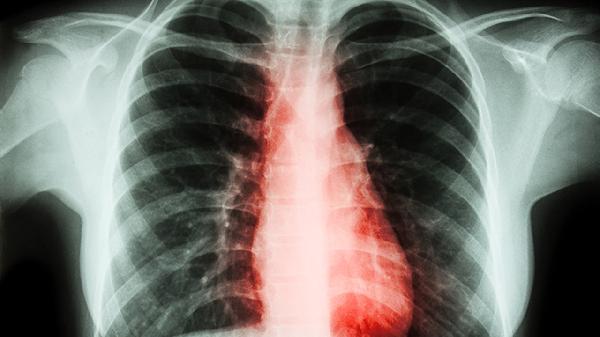

胸椎痛可能由肌肉劳损、骨质疏松、胸椎间盘突出、胸椎关节紊乱、强直性脊柱炎等原因引起。胸椎痛通常表现为局部疼痛、活动受限、放射痛等症状,可通过物理治疗、药物治疗、手术治疗等方式缓解。

胸椎痛可能与椎间盘退变、外伤等因素有关,通常表现为刺痛、肢体麻木等症状。患者可遵医嘱使用塞来昔布胶囊、甲钴胺片、盐酸乙哌立松片等药物,严重时需考虑椎间孔镜手术。